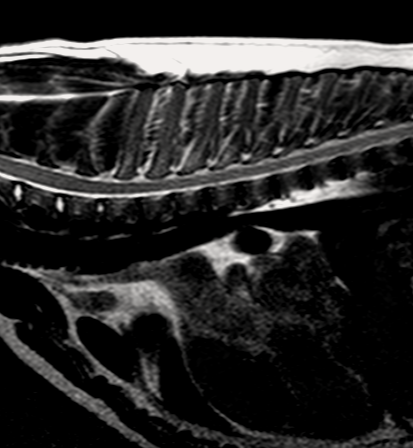

МРТ исследования проводятся на аппарате высокого качества Phillips Intera с напряженностью магнитного поля 1,5 Тесла. Позволяет максимально точно визуализировать анатомические структуры одинаково хорошо животному от 200г до 200кг

- Проведение мрт животному

- Подозрении на повреждения/ заболевания головного или спинного мозга,